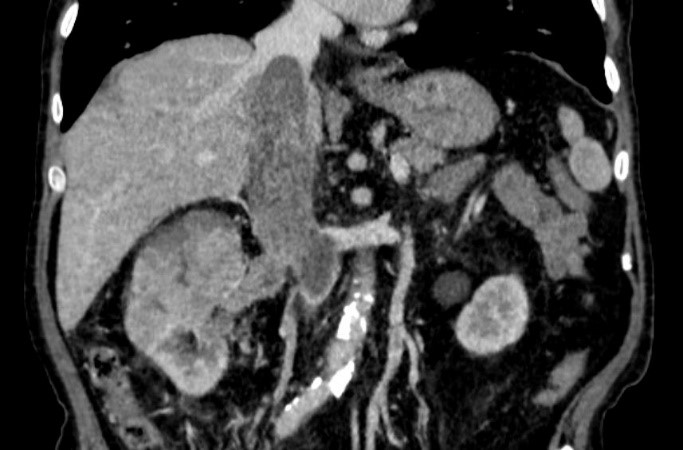

Examination: ultrasound - hypervascular tumor of the right kidney, tumor thrombus in the renal and inferior vena cava (Mayo III) (Fig. 1); MSCT - tumor of the right kidney, tumor thrombus in the inferior vena cava (Fig. 2); coronary angiography - critical stenosis of the coronary arteries (stenosis of the anterior interventricular branch (AIB) in the middle third up to 85-90%) (Fig. 3).

Figure 2: MSCT, right kidney tumor with the inferior vena cava thrombus